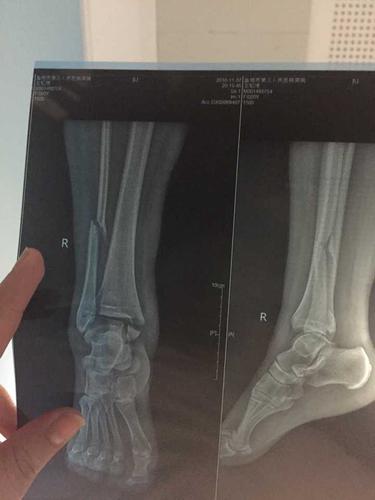

脚ct图片大全骨折,脚踝骨折ct图片清晰

骨折ct胫腓两处骨折 脚踝旋转

脚踝骨折有ct片请各位给点建议

骨折x光片图片

骨折x光片

脚踝骨折

胫腓骨骨折